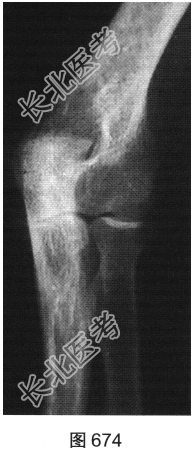

- [材料题] 患者女性,62岁,右侧肘关节肿胀、疼痛1年余。肘关节正侧位X线片及CT检查见图673~图676。

- 简答题1、请对该患者影像征象进行描述。

- 简答题2、根据题干中患者的临床表现及影像特征,请问该患者应首先考虑哪种疾病?